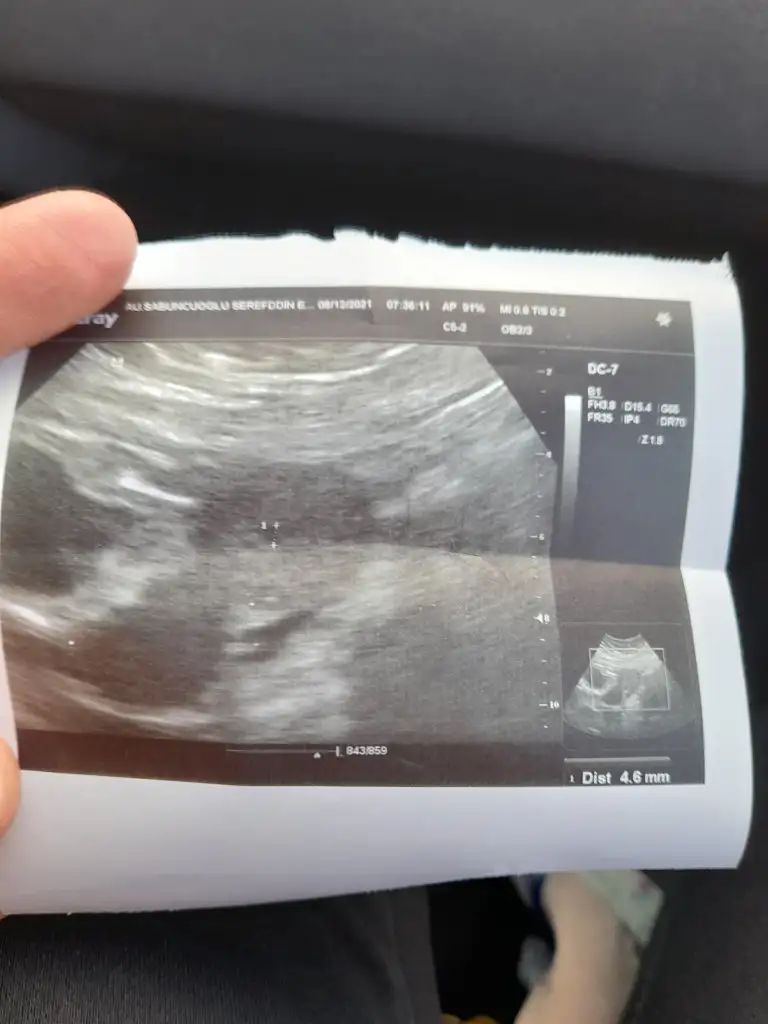

516 ydı canm evet erken davranmışız bana şüpheli kese dedi yani kese olduğuna 50/50 düşündü resmde atdm bak ben dr gidince 4000 olcak salı gdcem heycan dorukta

Eklentiler

• 20211208_092405.webp

20211208_092405.webp

23,7 KB · Görüntüleme: 55